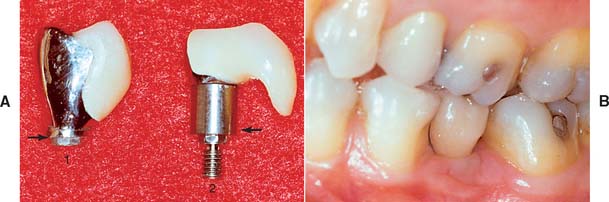

Fig. 13-47 Stage II interim restoration technique. A, View of missing maxillary right central incisor. B, Surgical template in position. C, Once the screw-shaped implant is in place, the fixture mount is luted to the surgical template with resin before it is unscrewed from the mouth. D, Analog attached to the fixture mount. E, Diagnostic stone cast prepared to position analog. F, Template placed back on diagnostic cast. G, Dental stone is flowed around the analog. The position of the analog is identical to the position of the implant in the mouth. H to L, A plastic sleeve is used for the fabrication of an interim restoration that can be delivered at stage II surgery.